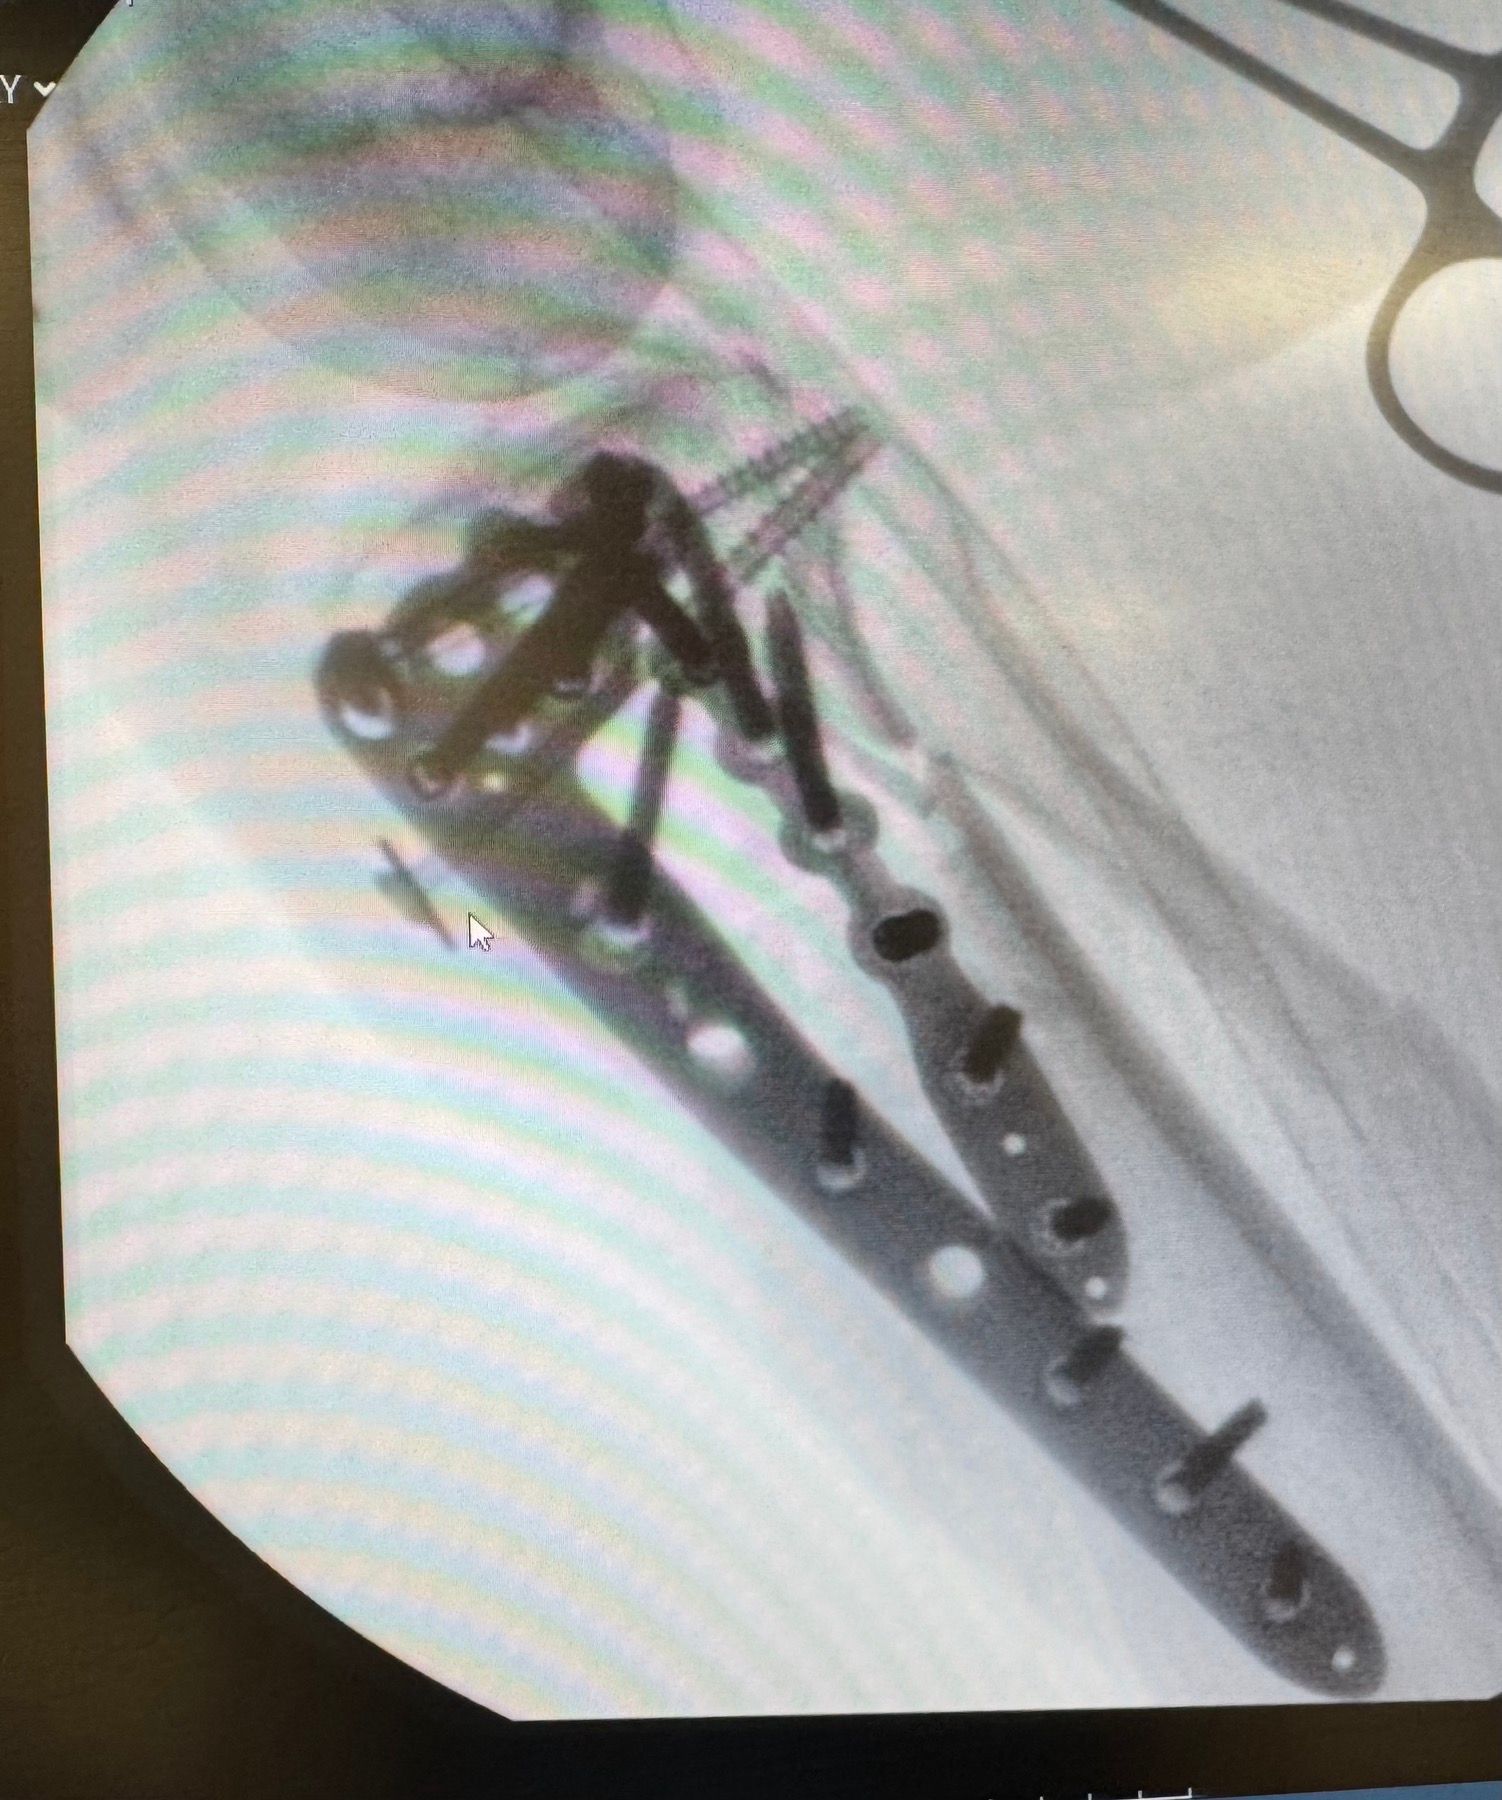

Μετά το χειρουργείο (αποτέλεσμα)